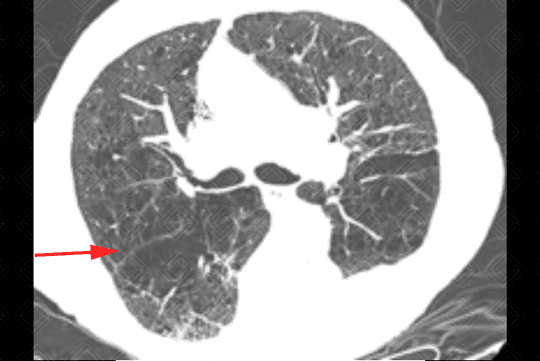

Texto alternativo para a imagem Figura 7. Créditos: Dra. Elazir Mota - Rio de Janeiro/RJ

Descrição das figuras 7 e 8: Tomografia computadorizada de tórax com aquisições axiais e sagitais evidenciando a presença de áreas de enfisema parasseptal nos lobos superiores dos pulmões em paciente tabagista (setas vermelhas). Observar que as áreas de enfisema parasseptal ocorrem na periferia dos pulmões, ou seja, em qualquer superfície pleural ou septos interlobulares.

• Tomografia computadorizada do tórax: Este método é mais sensível e específico que a radiografia de tórax na avaliação do enfisema. Tem sido empregado para detectar, quantificar e caracterizar a doença. A tomografia é capaz de diferenciar os vários tipos de enfisema, que pode ser classificado, de acordo com a região do ácino acometida, em proximal (centrolobular ou centroacinar - figuras 3, 4, 5, 6, 9, 10 e 11 ), distal (parasseptal - figuras 7, 8, 9, 10 e 11 ) ou todo ácino (panacinar ou panlobular).